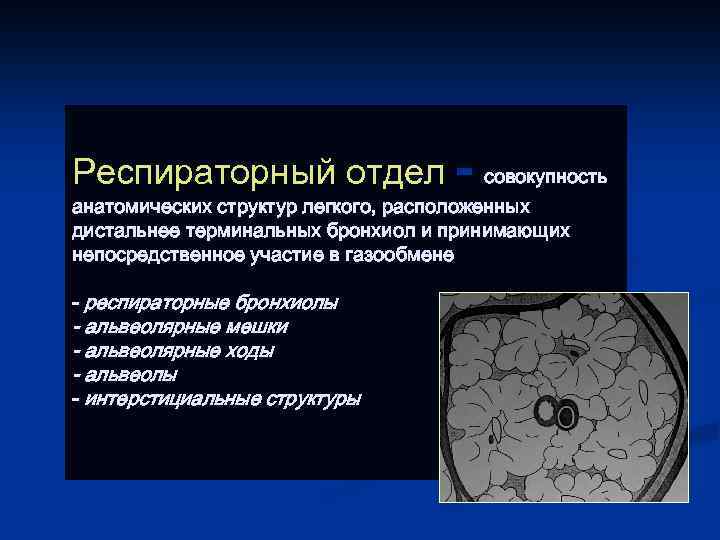

Респираторный отдел - совокупность анатомических структур легкого, расположенных дистальнее терминальных бронхиол и принимающих непосредственное участие в газообмене - респираторные бронхиолы - альвеолярные мешки - альвеолярные ходы - альвеолы - интерстициальные структуры